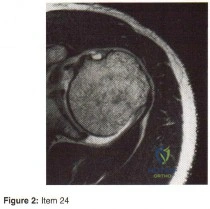

- MRI scan

- Bone scan

- Arthrogram

- Axillary lateral radiograph

- CT arthrogram

- CT scan of the shoulder

- Ultrasound of the shoulder

- An MRI scan of the shoulder

- An MRI scan of the cervical spine

- Electromyographic and nerve conduction velocity studies

- Immobilization in a sling and early passive range of motion exercises

- Immediate return to the operating room for exploration of the brachial plexus